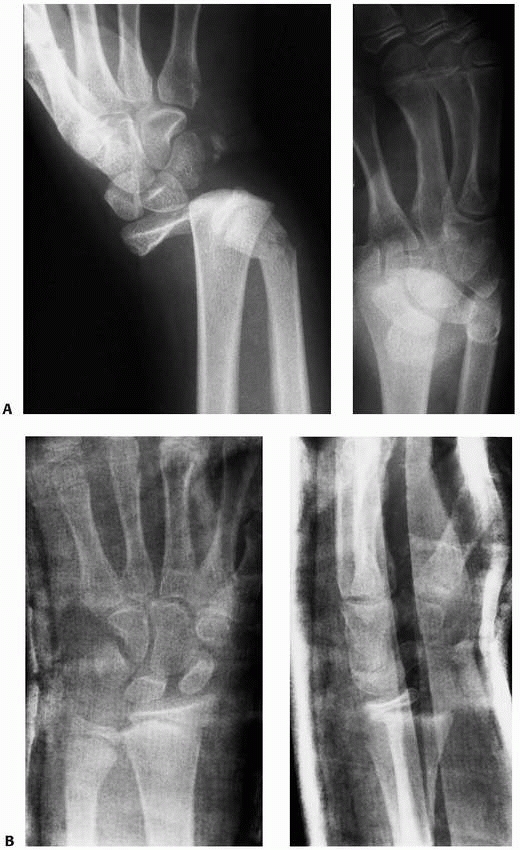

and angulation. Static AP and lateral radiographs can be diagnostic of

the fracture type and degree of deformity (Fig. 9-1). In adults,

the distal radial articular alignment averages 22 degrees on the AP view and 11 degrees on the lateral view.98,145,150,203,228

![]() |

|

FIGURE 9-2 Ossification of the distal radius. A. Preossification distal radius with transverse ossification in a 15-month-old boy. B. The triangular secondary ossification center of the distal radius in a 2-year-old girl. C. The initial ossification center of the styloid in this 7-year-old girl progresses radially (arrow). D. Extension of the ulnar ossification center into the styloid process of an 11-year-old. E. The styloid is fully ossified and the epiphyses have capped their relative metaphyses in this 13-year-old boy.

FIGURE 9-6

Technique for neutral rotation radiograph with wrist neutral, forearm pronated, elbow flexed 90 degrees, and shoulder abducted 90 degrees. |

FIGURE 9-7 A.

A 13-year-old boy presented 1 month after injury with a displaced and healed Salter-Harris type II distal radial fracture with obvious clinical deformity. B. Over the next 6 months, the patient grew 4 inches and the deformity remodeled without intervention. |